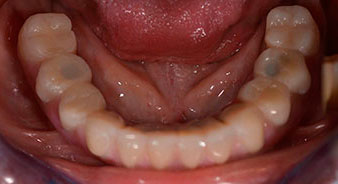

La paciente de 64 años se presentó con una dentición residual compuesta por las piezas dentales 38, 33 y 43 en el maxilar inferior y con una prótesis temporal fijada con ganchos en el maxilar inferior (figs. 1 y 2).

dentición residual

Fig. 1

Fig. 2